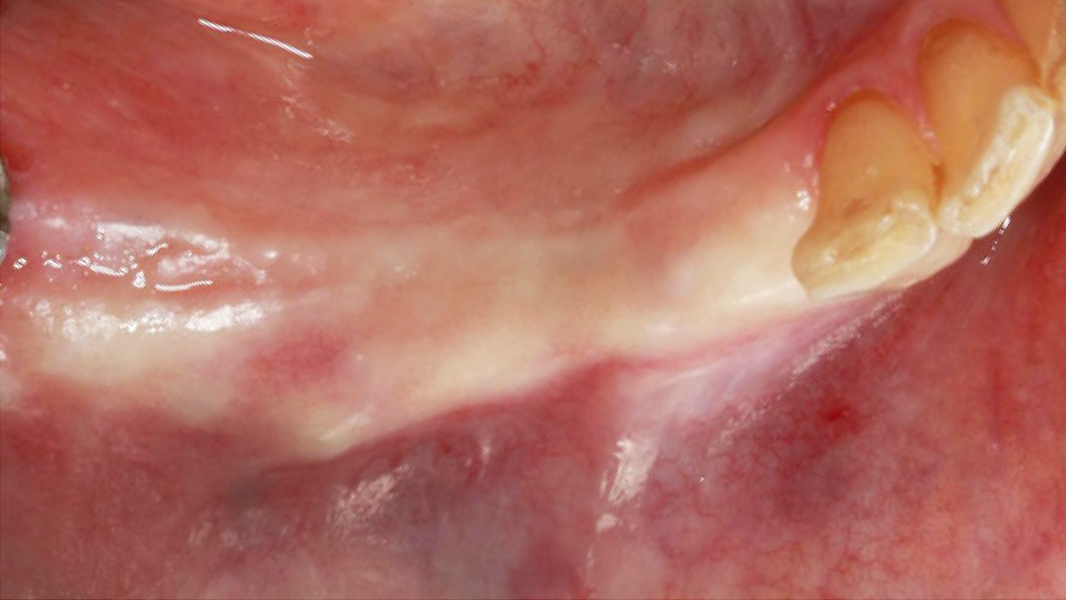

Klinische Erfahrungen MinerOss A + HYA

- Auf einer Skala von 1 bis 10 bewerteten die Kliniker die Heilung des Weichgewebes innerhalb der ersten zwei Wochen mit 8,8 bei den Erstanwendern.14, 17